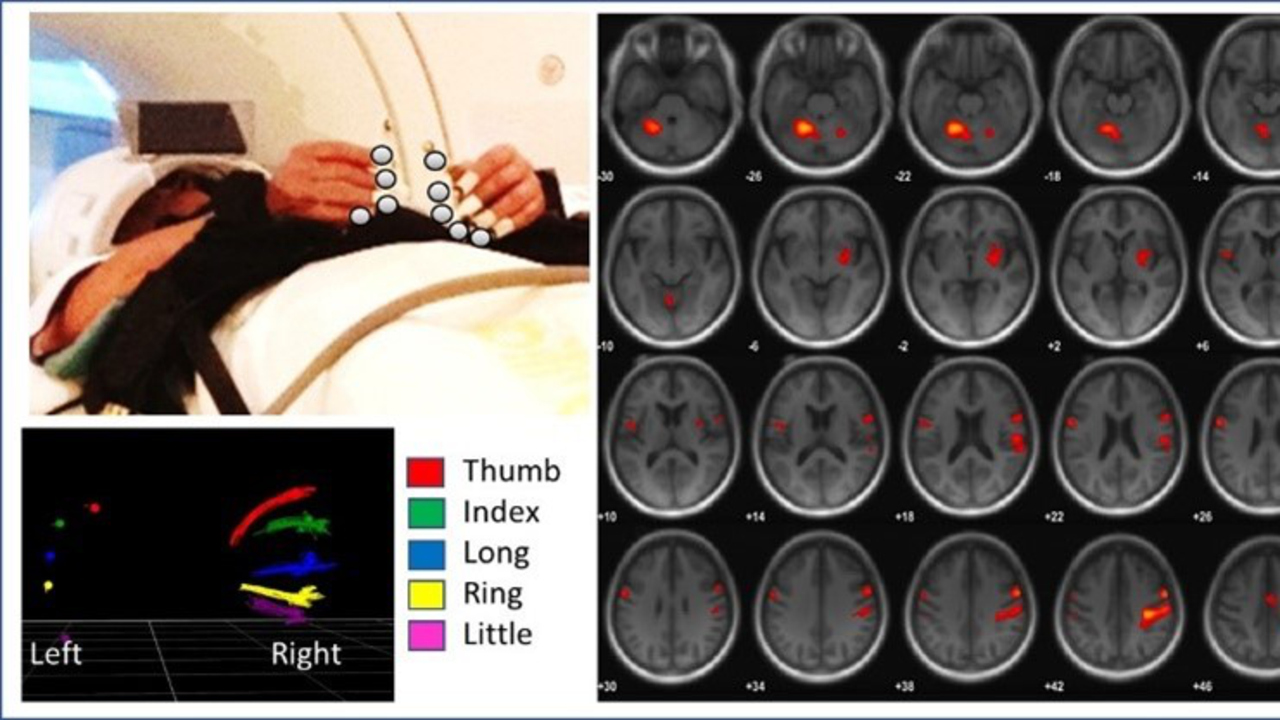

2. Fastställa förhållandet mellan motorisk funktion och underliggande neural aktivitet hos friska personer och ET-subtyper i en tvärsnittsdesign. Detta kommer att göras genom en ny kombinerad tidsserieanalys av multimodala data baserad på funktionell magnetresonanstomografi, fMRI, med samtidig registrering av tredimensionella arm- och benrörelser med hjälp av optiska specialkameror. Detta är en unik teknik som endast finns tillgänglig i ett fåtal laboratorier globalt och som ännu inte har tillämpats i samband med ET.